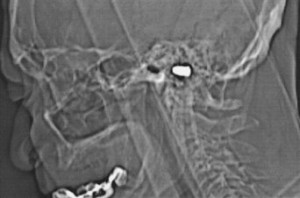

Los médicos decidieron hacerle una radiografía de la cabeza, que permitió “confirmar la veracidad de la historia”, señala Safarova. Los rayos X revelaron una silueta de bala aproximadamente en el centro de la cabeza. Para precisar mejor la localización del proyectil, le hicieron una serie de tomografías axiales computerizadas (TAC). La bala, de 1,2 centímetros de longitud y 7 milímetros de diámetro, “se encuentra claramente en el tejido cerebral”, indica la cardióloga.